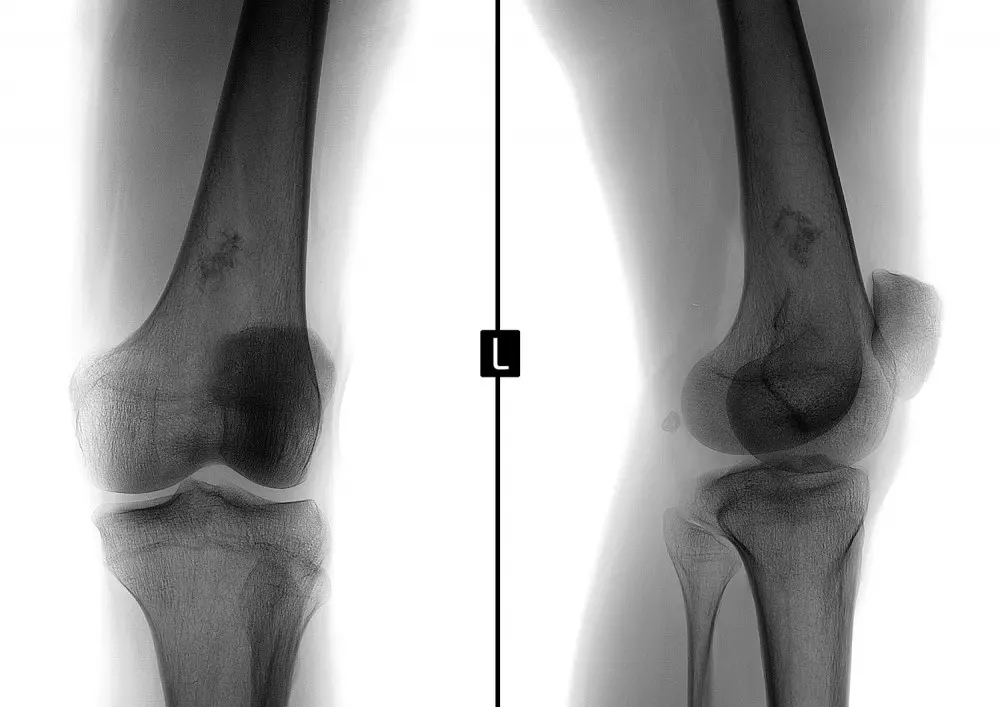

Kolano skoczka – metody lecznicze z punktu widzenia terapeuty

W dziale „Z praktyki gabinetu” znajdą Państwo tekst pt. „Kolano skoczka – metody lecznicze z punktu widzenia fizjoterapeuty”. Autor wskazuje na fakt, że zwiększona aktywność fizyczna, którą można zauważyć w ostatnich latach, sprzyja kontuzjom, przy czym szczególnie podatny jest na nie staw kolanowy o skomplikowanej budowie anatomicznej. Wśród tych kontuzji można wymienić właśnie kolano skoczka. „To uszkodzenie więzadła rzepki w miejscu, gdzie łączy się ono z rzepką. W tym newralgicznym miejscu sumują się różnego rodzaju mikrourazy, które w perspektywie czasu powodują degenerację tkanek” − pisze dr n. med. Kamil Klupiński.